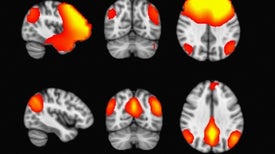

Constant Shifts between Mental States Mark a Signature of Consciousness

Both of two essential brain networks that switch roles—one is on when the other is off—shut down in unresponsive individuals